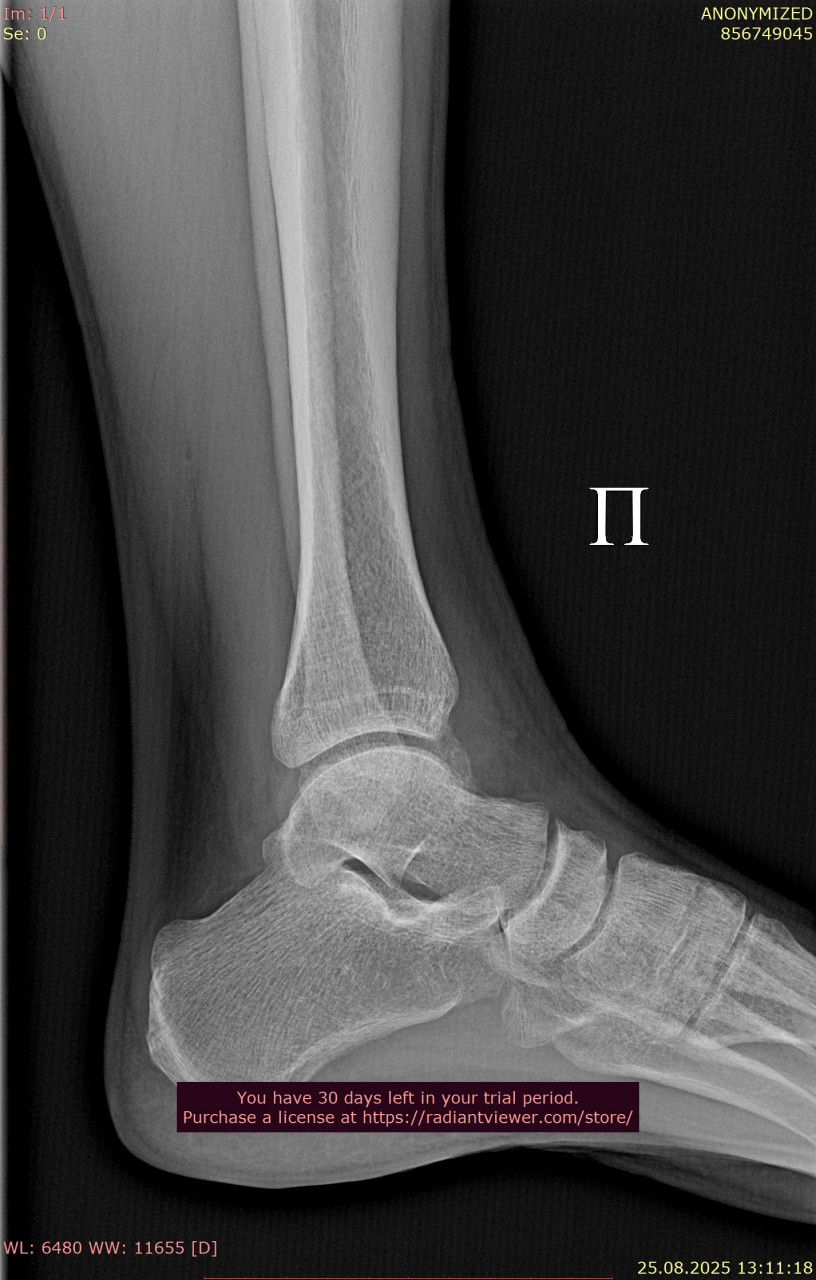

Прикрепляю снимки лодыжки от 23.06.2025, когда был перелом

Сравнивая ваши снимки от 23.06 и 25.08:

- Линии переломов на костях стопы и области голеностопного сустава больше не прослеживаются чётко, видна формирующаяся костная мозоль – это признак заживления.

- Смещения отломков нет, контуры выровнены, что говорит о правильном срастании.

- Для срока 2 месяца после перелома динамика положительная, основные признаки консолидации присутствуют. Обычно к этому времени разрешают постепенную нагрузку, но полное снятие опоры (ходьба без костылей, тростей) должно быть постепенным и согласовано с вашим травматологом.

По вашим новым снимкам от 28.07 и контрольным от 25.08 признаков несращения или смещения нет т.к переломы в области стопы и голеностопного сустава консолидируются, костная мозоль выражена, контуры ровные. То есть прочность костей уже достаточна, чтобы постепенно начинать ходьбу без ходунков. То, что вы пока ставите ногу без активного сгибания пальцев, допустимо и так обычно и бывает на этапе ранней нагрузки. Постепенно с помощью ЛФК и разминки подвижность пальцев и стопы восстановится. Перегрузки голеностопа при аккуратной ходьбе на полной стопе сейчас не будет, наоборот  умеренная нагрузка нужна для правильного ремоделирования костной ткани.